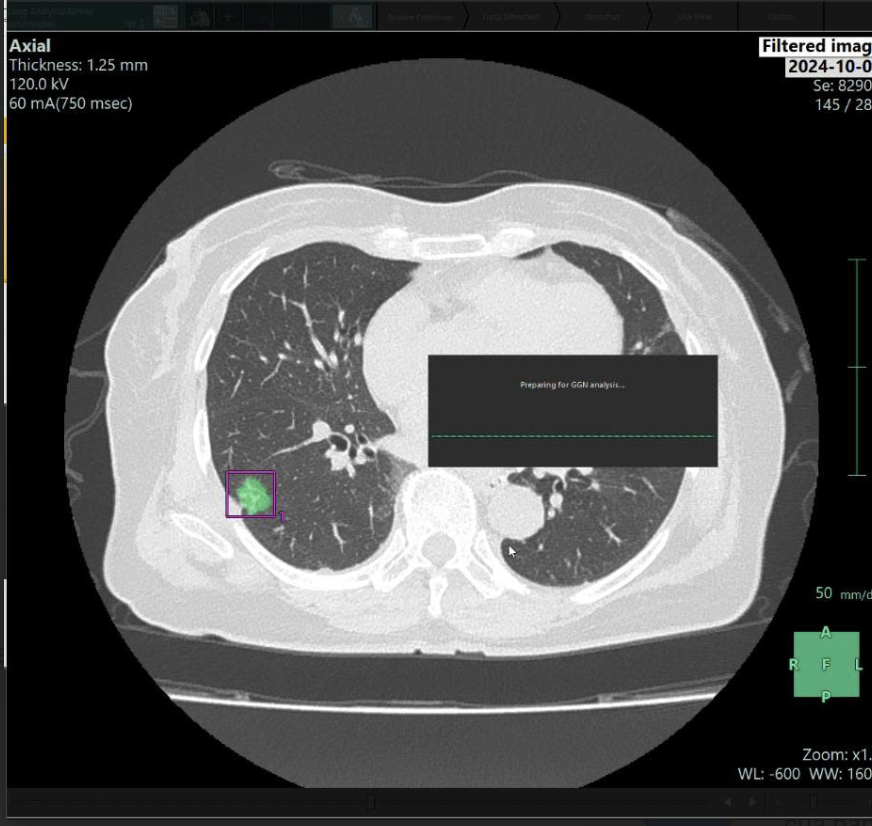

Còn tại Nura, liều tia X đã được giảm đến 97% so với thông thường, đảm bảo an toàn cho cơ thể nên phù hợp để tầm soát định kỳ. Lấy ví dụ thực tế, Ths.Bs Nguyễn Tất Đạt – Bác sĩ chuyên khoa Chẩn đoán hình ảnh tại Trung tâm Nura cho biết: Có khách hàng nữ hơn 40 tuổi, được phát hiện ung thư phổi dù trước đó được chẩn đoán viêm phổi tại cơ sở khác và điều trị suốt một tháng. Nhưng khi đến kiểm tra tại Nura, sau khi được chụp CT (giảm hơn 90% liều tia X khi chụp cả vùng ngực và bụng), hình ảnh vẫn rất rõ nét nhờ AI xử lý nhiễu và khách hàng này may mắn được phát hiện một nốt phổi kích thước 10mm.

Hệ thống AI phân tích hình ảnh và đưa ra cảnh báo: Bờ tổn thương không đều, không rõ các mạch máu, mật độ tế bào cao và tỷ lệ nốt đặc gần 70%. Dựa trên gợi ý từ AI và kinh nghiệm lâm sàng, bác sĩ đã chỉ định sinh thiết. Kết quả xác nhận ung thư biểu mô tuyến phổi giai đoạn 1, đây được coi là thời điểm vàng để điều trị hiệu quả và giảm tối đa nguy cơ di căn.